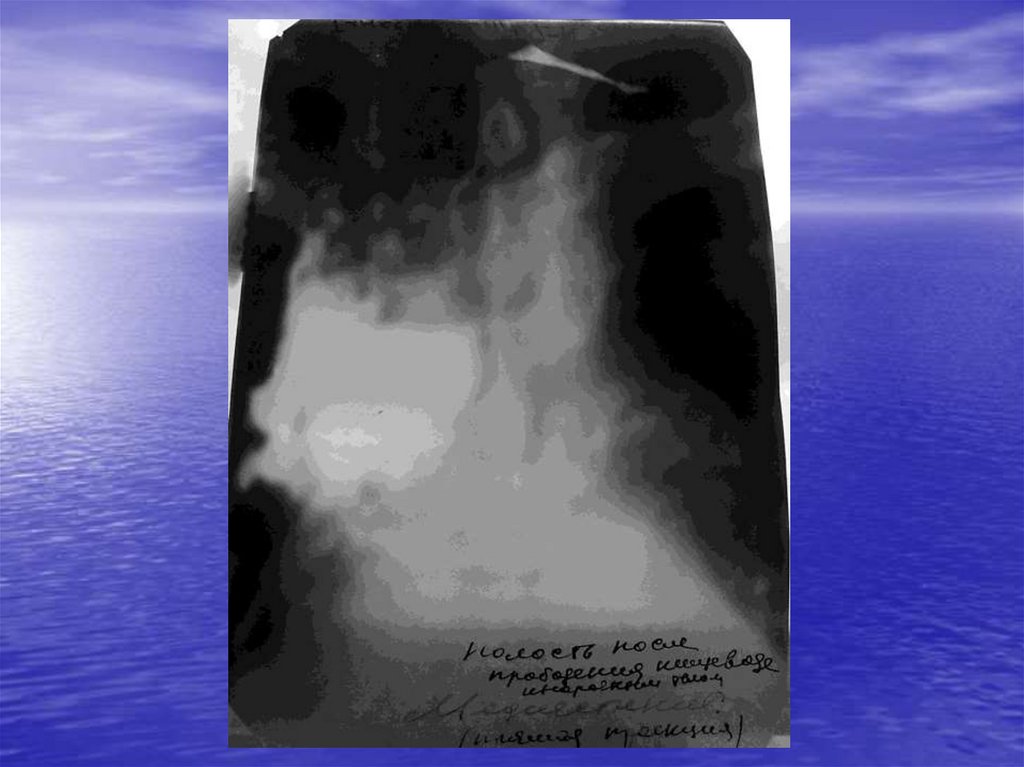

А) Перфорация стенки пищевода

В) Спонтанный разрыв пищевода

8. Клинические симптомы при медиастините